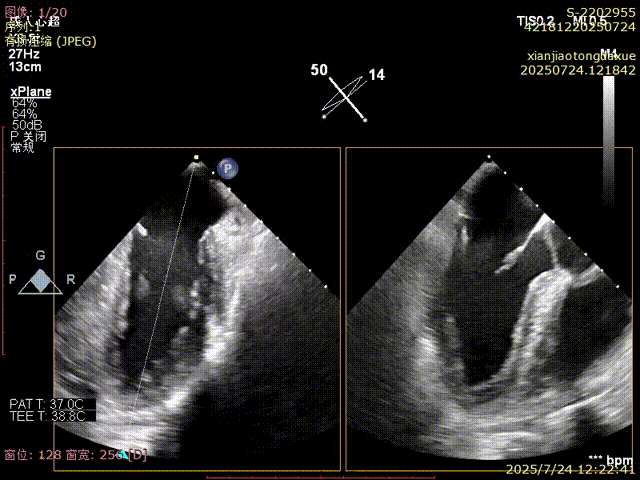

影像评估提示病变位于二尖瓣三区交界,瓣膜结构复杂,患者低氧血症,无法耐受体外循环,传统外科修复风险高,微创TEER治疗成为优选方案。手术团队采用ValveClamp® II型夹进行精准定位与夹合。通过麻醉快速通道迅速、高效完成手术,术中经经食道超声(TEE)实时引导,夹子精准落点于三区交界,瓣叶抓取稳定,夹合线条自然,反流显著改善,术后即刻拔除气管 ,插管,术后无并发症,心功能恢复良好。

3D确认夹合位置

3D视角下反流情况